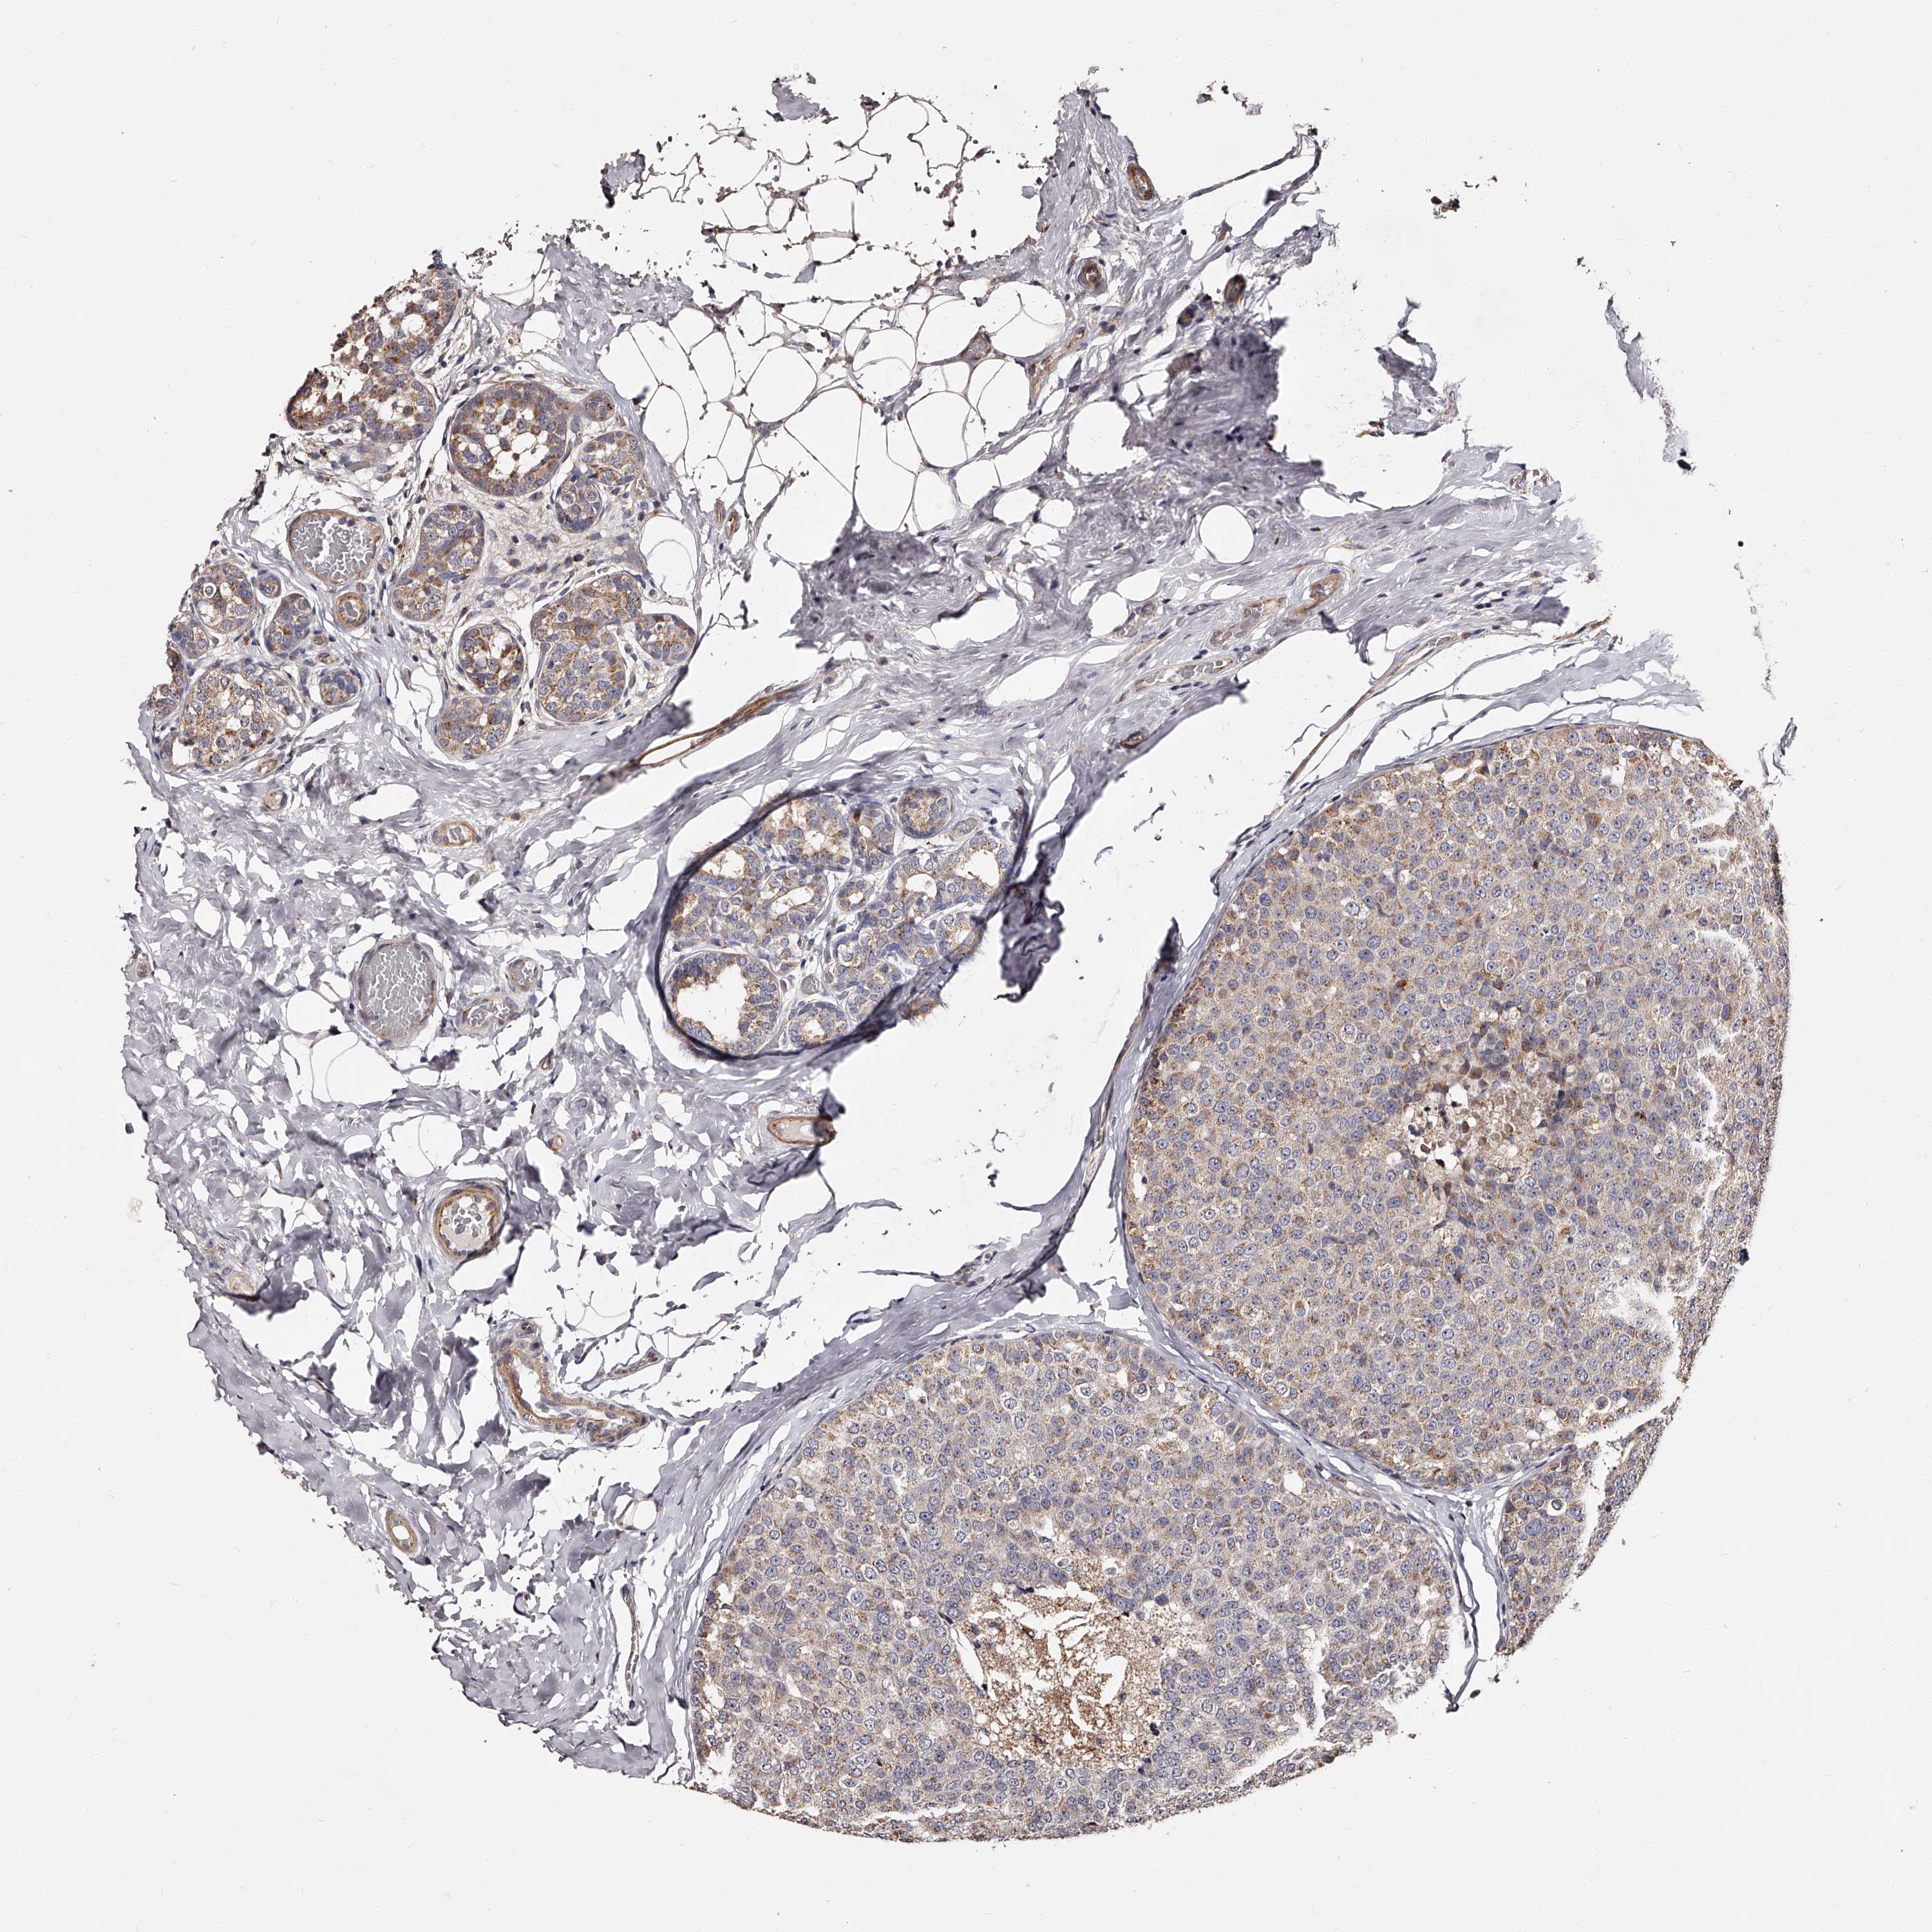

CANCER BREAST CANCER Show tissue menu

BRCA TCGA BRCA VALIDATION PROTEIN EXPRESSION